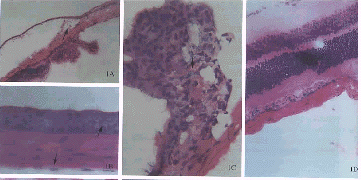

图1 对照组的角膜(A)、虹膜(A,F)、睫状体(A)和视网膜(A,D)。玻璃体腔内注射DOSPER与pGME-7Zf(+)质粒混合液后1周基因转移情况:角膜上皮细胞和内皮细胞(B)、睫状体(C)、虹膜(G)、视网膜节细胞层、光感受器层及色素上皮细胞(E)均可见β-半乳糖苷酶基因的阳性表达 图2 尾静脉注射DOSPER与pGME-7Zf(+)质粒混合液后1周视网膜基因转移情况:脉络膜(a)、视网膜色素上皮细胞(b)、光感受器(c)及节细胞(d)均可见β-半乳糖苷酶基因的阳性表达 Fig.1